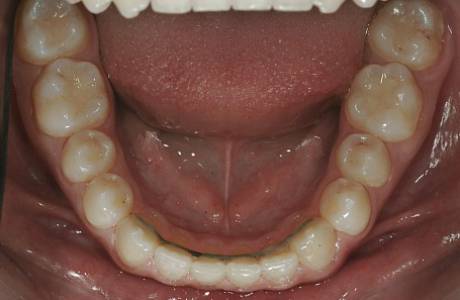

После лечения

Прикус восстановлен, зубы выровнены.